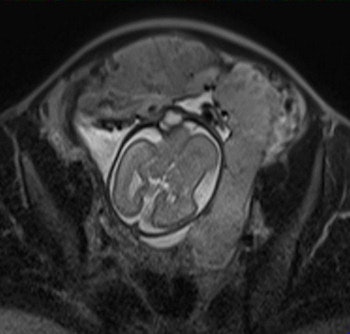

Their retrospective study included 25 pregnant women (mean age 35.16) -- 12 with histopathologically proven placental invasion and 13 without to act as a control -- who were investigated by prenatal MRI without IV contrast at three hospitals using three different 1.5-tesla MRI units (Magnetom Symphony, Siemens Healthcare; Intera, Philips Healthcare; Signa, GE Healthcare). The women underwent MR imaging between June 2007 and December 2009 after obstetrician referral for suspected placental invasion upon standard pregnancy ultrasound exams. The MRI protocols were similar and included T1-weighted volume interpolated gradient-echo MR sequences in the sagittal and axial plane, single-shot fast spin-echo T2-weighted MR sequences, and true fast imaging with steady-state precession in the axial, sagittal, and coronal planes.

Two senior radiologists with more than five years of practical experience in abdominal MRI and two junior radiologists with less than three years of abdominal MRI experience blindly and independently reviewed MR exams for six previously defined MR features described in the literature as useful for predicting placental invasion. The features included dark intraplacental bands on T2-weighted images, a focally interrupted myometrial border, heterogeneous intraplacental signal intensity, abnormal uterine bulging, "tenting" of the bladder, and infiltration of the adjacent pelvic organs.

In normal patients, the uterus presents as an inverted pear-shape organ. At MRI, the normal placenta appears as a soft-tissue structure, located along the uterine walls, with variable morphology and homogeneous, intermediate, signal intensity on T2-weighted images. In Alamo's study, T2-hypointense placental bands, a focally interrupted myometrial border, infiltration of the pelvic organs, and tenting of the bladder proved to be the best signs of predicting placental invasion.